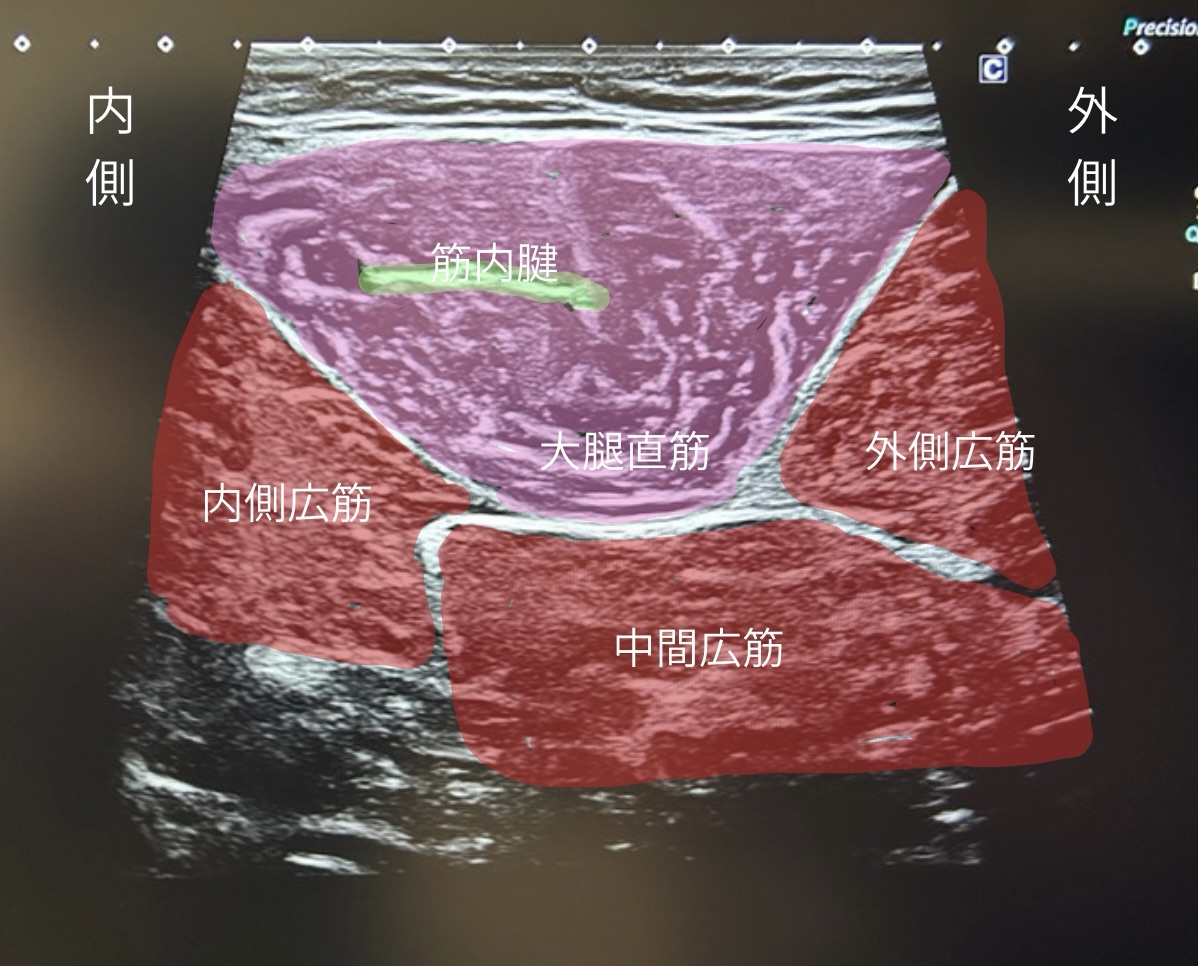

▶ エコー(超音波検査)

・出血や腫れの有無

・筋肉や腱の損傷、骨の付着部の損傷(裂離骨折)の確認

・筋肉の収縮動き